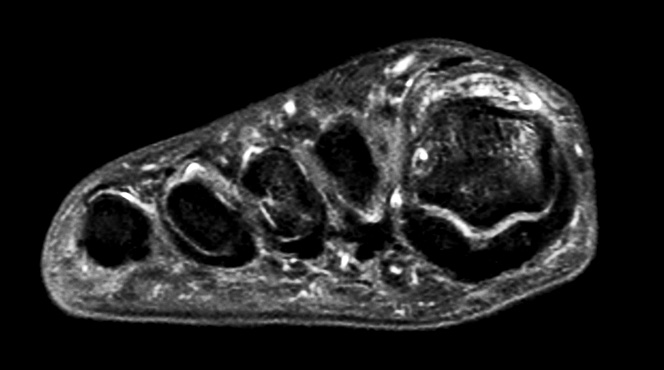

Axial PDw mDIXON TSE  (water only)